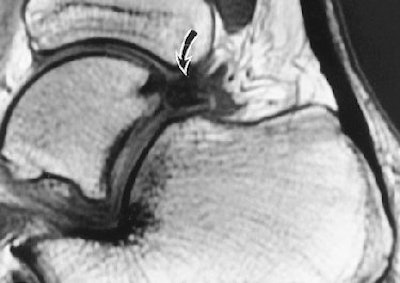

For this retrospective study, they included 10 professional soccer players who had sustained an inversion injury of the ankle in the neutral position. Posterior impingement then developed.

All the players had undergone physical rehabilitation but still developed posterior pain. Both noncontrast and contrast-enhanced MR imaging was done. Ultrasound exams were performed with a 10-15 MHz transducer (Antares, Siemens Medical Solutions, Malvern, PA; ATL 5000, Philips Medical Systems) to evaluate the posterior capsule tissues including a Doppler study of soft-tissue abnormality.

For the injection therapy, a 20- or 23-gauge needle was inserted directly to the abnormal area of the posterior capsule. Then, 40 mg of triamcinolone acetonide and 3 mL of 0.5% bupivacaine hydrochloride were injected into the abnormal tissues. If an os trigoum was present, the needle was moved on to the ossicle.

According to the results, all patients had posterolateral hypoechoic capsule thickening that was nodular and localized to the lateral aspect of the lateral talar process or os trigonum. All 10 patients tolerated the injection procedure with no immediate complications. They also reported ankle improvement after the bupivacaine shot.

| Axial sonography image of os trigonum (O) and adjacent fragment (Fr) obtained during injection shows nodular synovitis (asterisk) with needle (arrowheads) placed during infiltration and injection. Further infiltration was performed around fragments. Robinson P and Bollen SR, "Posterior Ankle Impingement in Professional Soccer Players: Effectiveness of Sonographically Guided Therapy" (AJR 2006; 187:W53-W58). |

The median follow-up time was 26 months for all players. At this juncture, eight out of 10 patients with posterolateral synovitis and no os trigonum had no residual or recurrent symptoms. The remaining two players who did have posterolateral synovitis and os trigonum on imaging experienced a recurrence of symptoms and underwent repeat injection with ultrasound guidance. One player remained pain-free after the second session; the other required endoscopic resection.